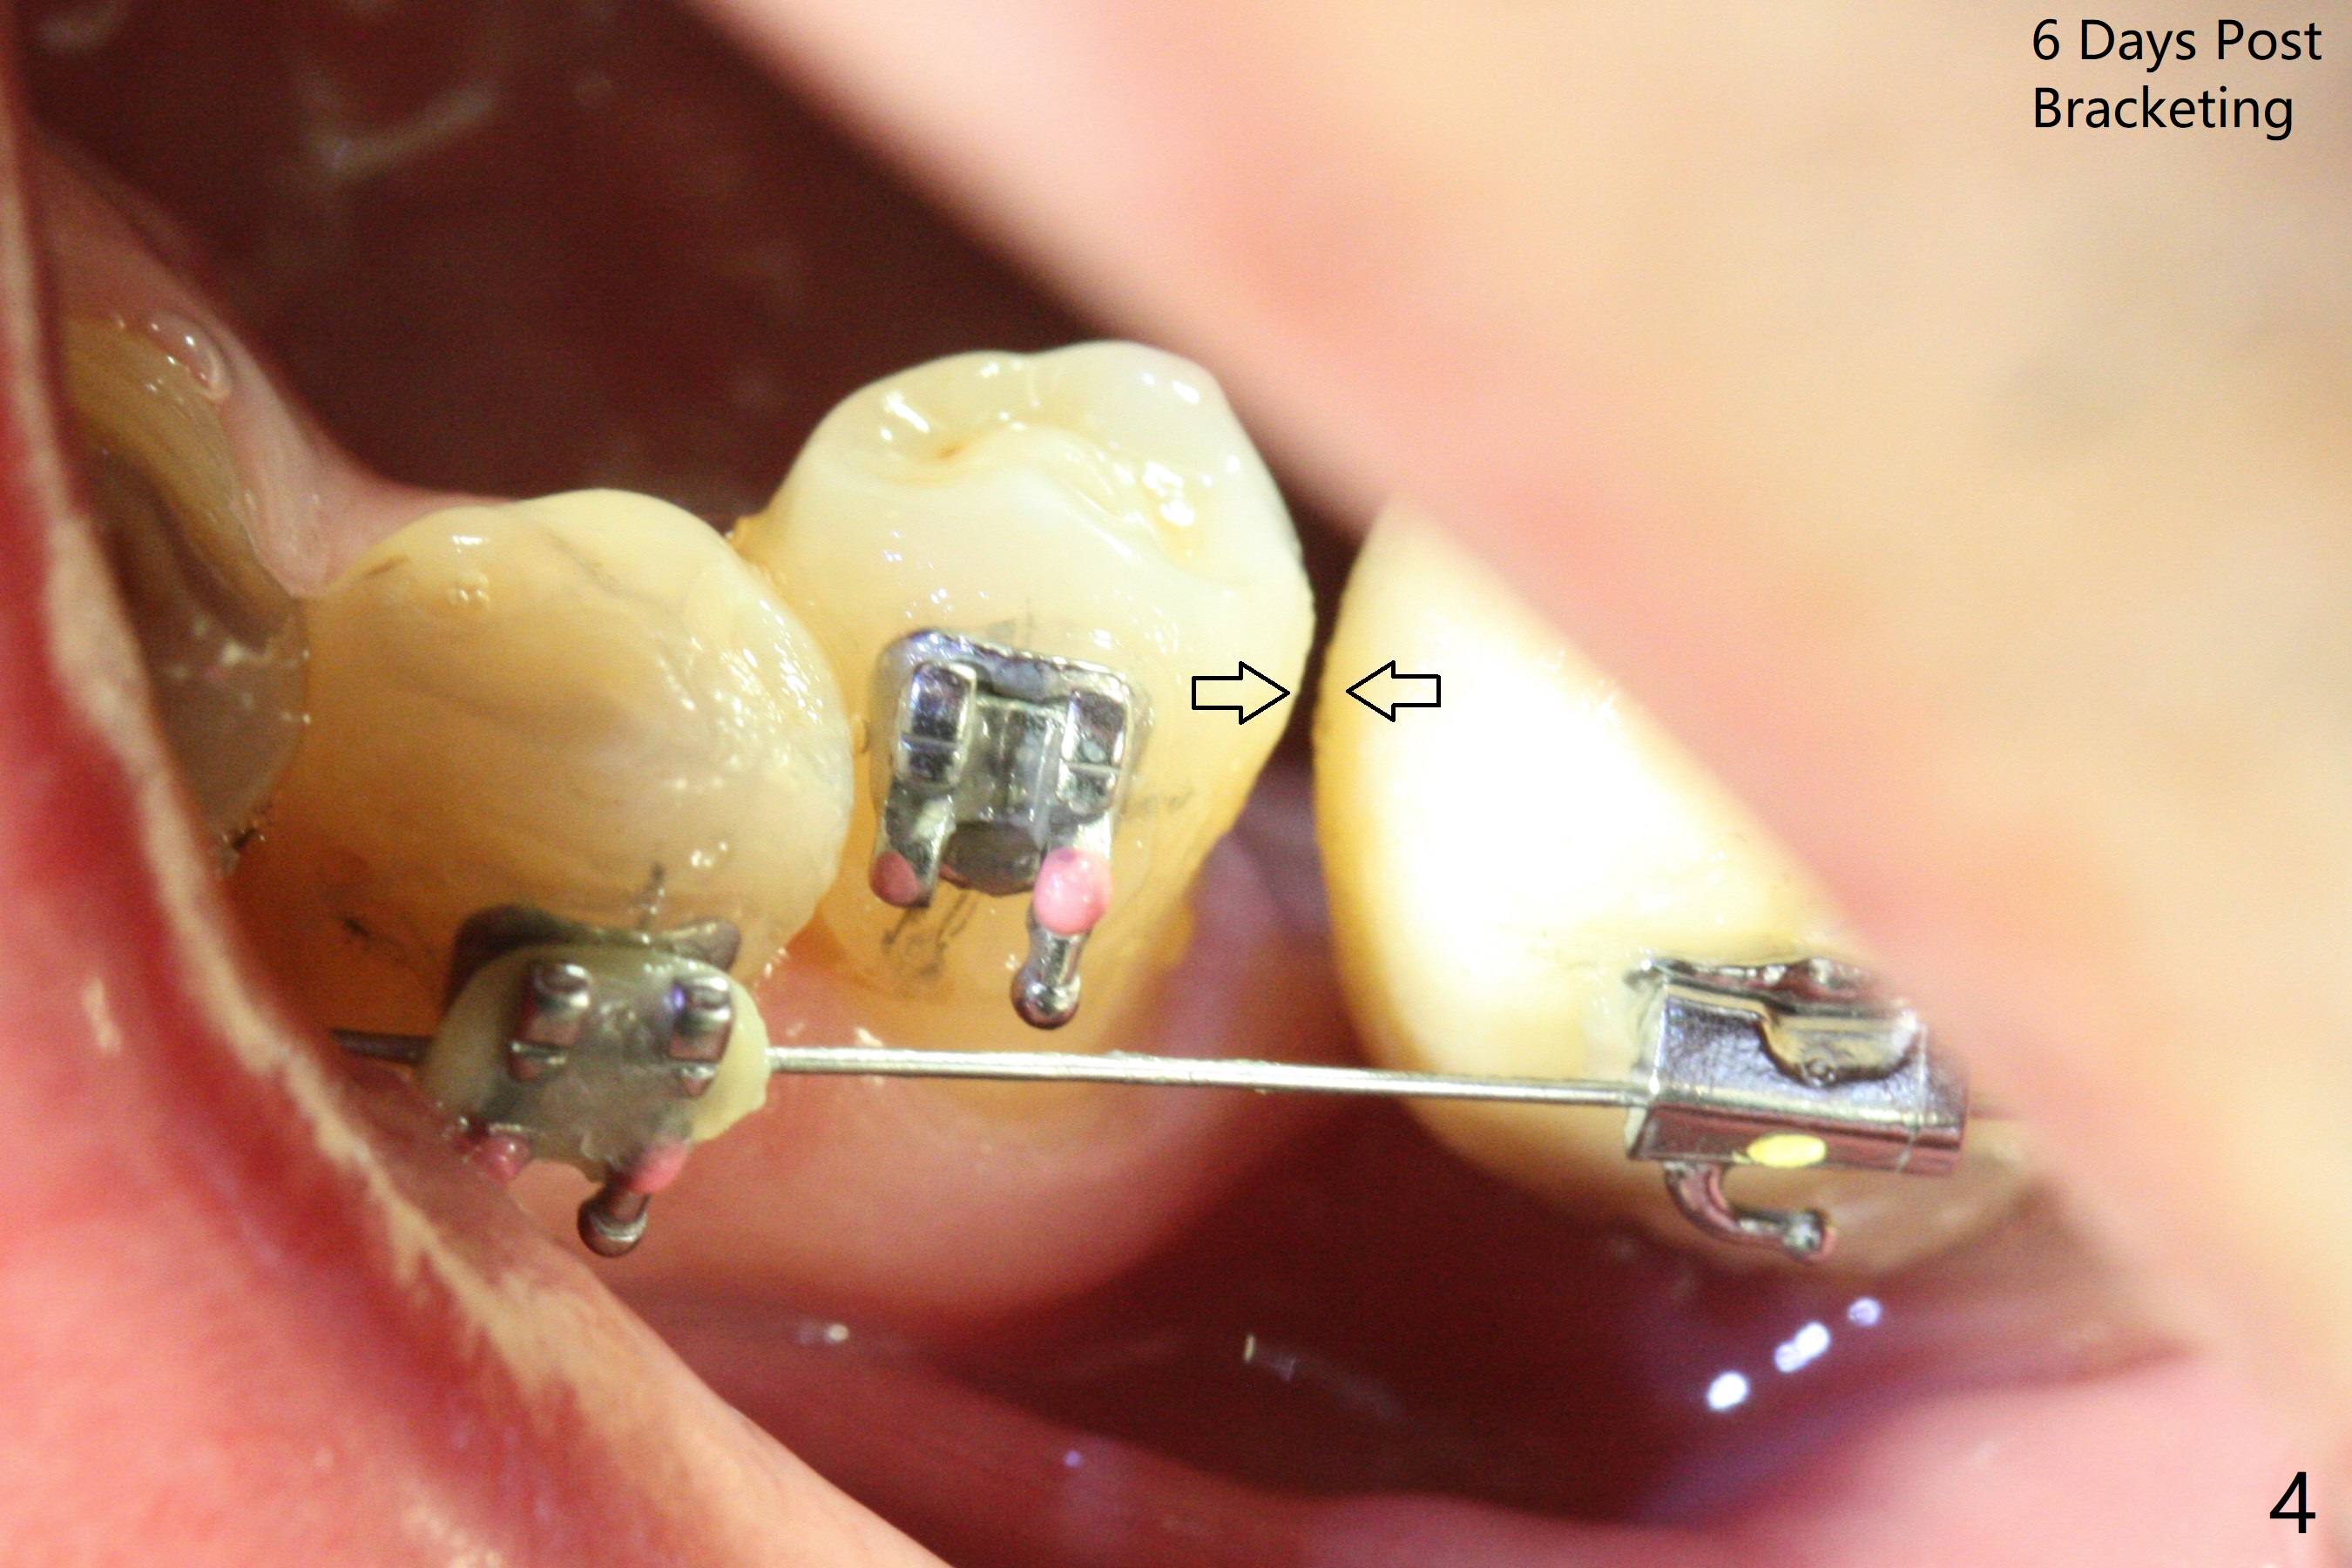

Two weeks post provisionalization over implants at #18 and 19 (4.5 months postop), acrylic is added to the provisional (Fig.1 *) and composite is placed on the other side (Fig.2 *) for clearance (Fig.3). Six days post bracketing, the diastema between LL5 and 6 decreases (Fig.4 between arrows, as compared to Fig.3), suggesting uprighting and distalization of the affected tooth. The diastema increases by trimming the mesial surface of LL6 provisional (Fig.5 *) prior to power chain placement. More acrylic is added to the occlusal surface of LL 6 and 7; more composite to that of UR3 (as compared to Fig.2) for clearance. Power chains change every week. LL5 is uprighted and distalized 1.5 months post banding (Fig.6,7 (14 niti)). Anterior brackets will be placed to correct LL2 cross bite next visit. Three weeks post open coil spring (5 months post initial banding), there is a space between LL2 and 3 (Fig.8) and between LL3/4 (Fig.9). The latter reduces instantly post power chain between LL3 and 6 (Fig.10). There is enough space for LL2 and sling shot is used to correct the cross bite 6.5 months post initial banding (Fig.11). The cross bite is corrected in 1.5 months after occlusal clearance is established (Fig.12). The lower left alignment is within normal limit, although in cross bite with the opposing dentition, immediate post molar crown cementation (Fig.13).